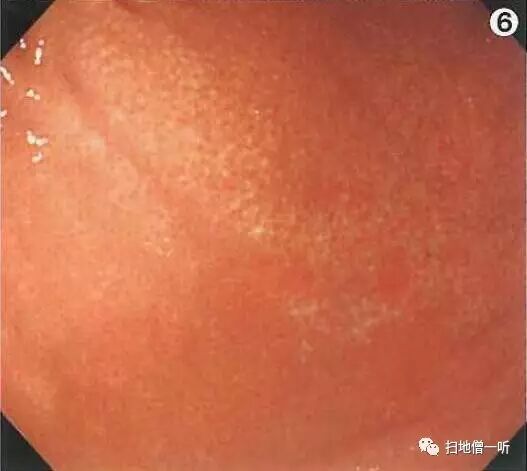

A:胃癌在图3及图6。HP未感染胃癌。

胃粘膜RAC阳性表现,提示HP未感染粘膜。胃体下部小弯侧可见小片状褪色粘膜。图3和图6是两个角度观察同一处病变。

靛胭脂喷洒然后后边界不清,表面无凸凹变化,为IIb型病变。无萎缩的胃底腺区域发现退色调病变,应怀疑印戒细胞癌。

最终病理诊断:

胃体下部小弯,O-IIb,4mm,sig,T1a (M),UL(-)

小结:HP未感染背景下退色调病变应注意着重观察。